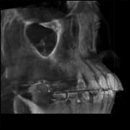

CTやレントゲンを使った徹底的な検査・診断・チェック

根管治療では、マイクロスコープや拡大鏡を使うことにより肉眼では見づらい根管をはっきり見ることができます。

しかし、複雑な歯の根の中を治療するには、それらだけでは万全ではありません。

当院では、CTやレントゲンを使って目に見えない部分の問題やポイントも見逃しません。

CTやレントゲンのデータは、治療前の徹底的な検査や診断に役立てるほか、治療後のチェックにも使用されます。

CT画像の例